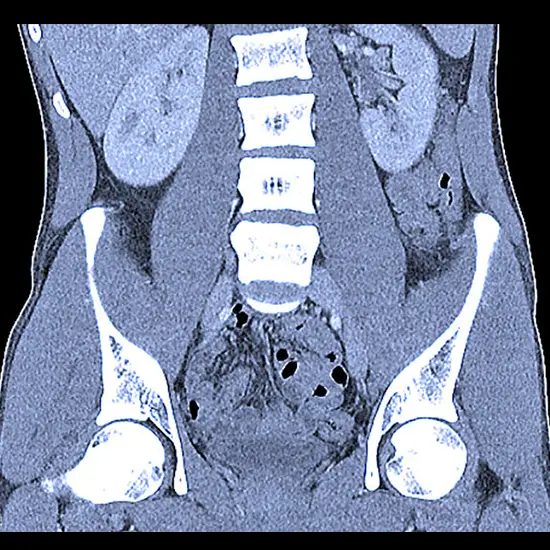

A computerised tomography (CT) urography is a type of imaging exam used to assess the urinary tract. The urinary tract consists of the kidneys, the bladder, and the tubes (ureters) that transport urine from the kidneys to the bladder.

A CT urography generates multiple images of a slice of the area of your body being studied, including bones, soft tissues, and blood vessels, using X-rays. These images are then transferred to a computer where they are quickly reconstructed into detailed 2D images.

An X-ray dye (iodine contrast material) is injected into a vein in your hand or arm during a CT urography. The dye flows into the kidneys, ureters, and bladder, highlighting each structure. X-ray images are taken at specific points during the exam so that your doctor can see your urinary tract clearly and assess how well it is working.

The kidneys, ureters, and bladder are examined using a CT urography. It allows your doctor to examine the size and shape of these structures in order to determine if they are functioning properly and to look for any signs of disease that may affect your urinary system.